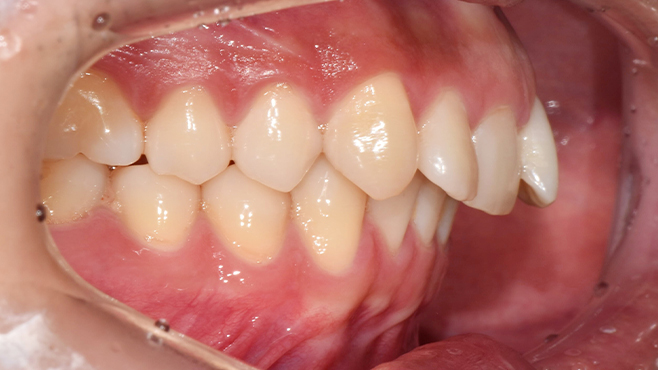

맞는 건 괜찮은데… 충치는 못 참겠습니다|20대 격투기 선수 치과 방문기

2026.02.06